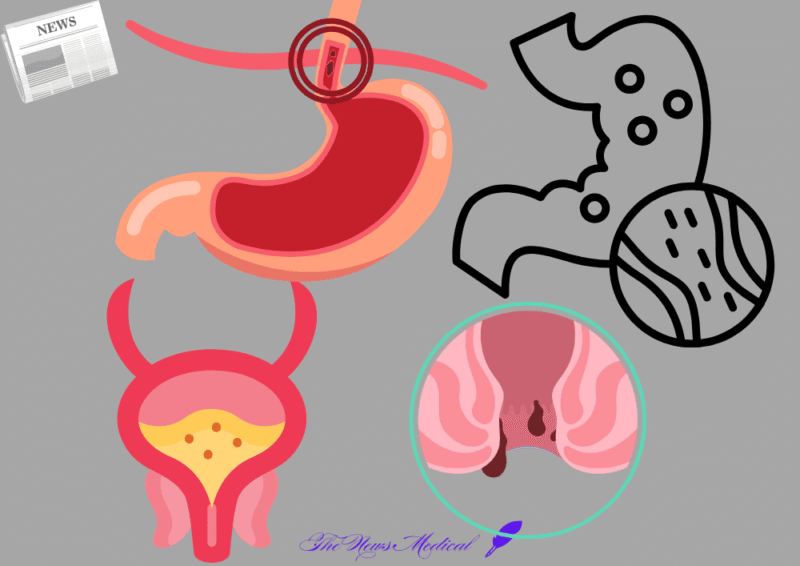

전립선암 수술 후 비뇨기과적 문제, 합병증은? 전립선암의 급증과 치료법 변화 전립선암은 현재 국내에서 남성 암 중 가장...

괄약근 약화, 괄약근에 대한 이해 넓히고 적절한 관리가 필수 현대인들은 다양한 건강 문제에 직면하고 있으며, 특히 소화기...

전립선비대증 방치하면 큰병 부른다. 최적의 치료법은? 50대 이상 남성이라면 누구나 한 번쯤 겪는 소변 문제. 밤새 몇...